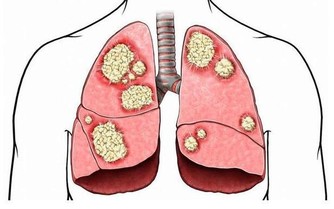

癌症先兆是可以警示我們應該及早預防癌症,但是我們往往會忽視這些疾病徵兆,以至於「病來如山倒」。

今天小編想要和大家分享的是胃癌的一些常見徵兆。